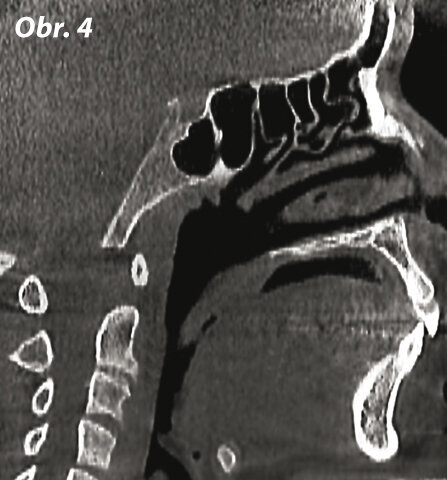

Sagitální rovina (obr. 3, 4)

Sagitální rovina rozděluje lebku na dvě symetrické části. Umožňuje vyšetření dvou segmentů: pravého a levého.